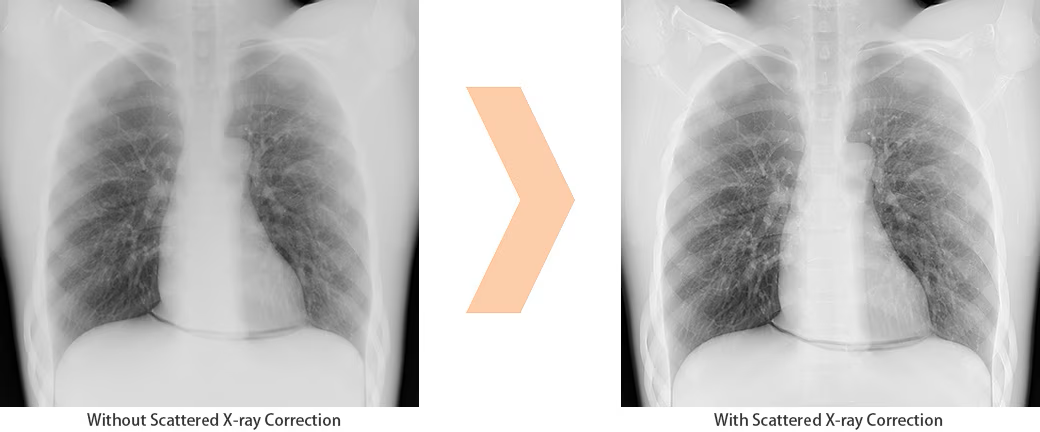

Scatter Correction enables grid-less radiography OPTION

The system can be equipped with a function to remove scatter noise and improve image contrast, making it possible to perform exposures without the use of a grid therefore making it easier to handle FPDs.